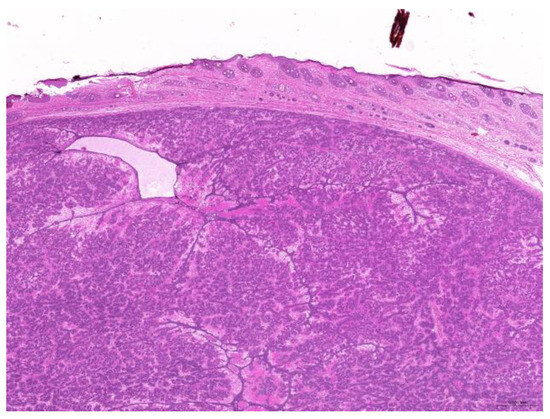

Of the 85 biopsy samples, the most commonly affected system was the integumentary system (48.2%, 41/85), followed by the reproductive system (42.4%, 36/85), the digestive system (8.2%, 7/85), and the urinary system (1.2%, 1/85) (Table 3). Of the 41 rabbits with an affected integumentary system, 39 had neoplastic and two had non-neoplastic disorders. The median age of these affected rabbits was 87 (12–149) months. There were 15 females and 26 males, with a female-to-male ratio of 0.54:1. The most common integumentary diagnosis was fibrosarcoma (29.3%, 12/41) (Figure 1), followed by trichoblastoma (19.5%, 8/41) (Figure 2), fibroma (9.8%, 4/41) (Figure 3), lipoma (7.3%, 3/41), mammary gland adenoma (7.3%, 3/41), and mammary gland adenocarcinoma (4.9%, 2/41) (Figure 4), among others. The median age of the rabbits with fibrosarcomas was 108 (54–126) months. Of the 12 cases with fibrosarcoma, 4 were females and 8 were males, with a female-to-male ratio of 0.5:1. The tumors were located on the neck, chest, abdomen, and extremities. The median age of the rabbits with fibromas was 101 (48–108) months. All four of these were males, with tumors exclusively located on the chest. Myxosarcoma was diagnosed in a 108-month-old male rabbit, with the tumor located on the left elbow (Figure 5).

Figure 2. Trichoblastoma. Neoplastic cells are arranged in trabeculae (scale bar = 500 µm). Hematoxylin and eosin staining.